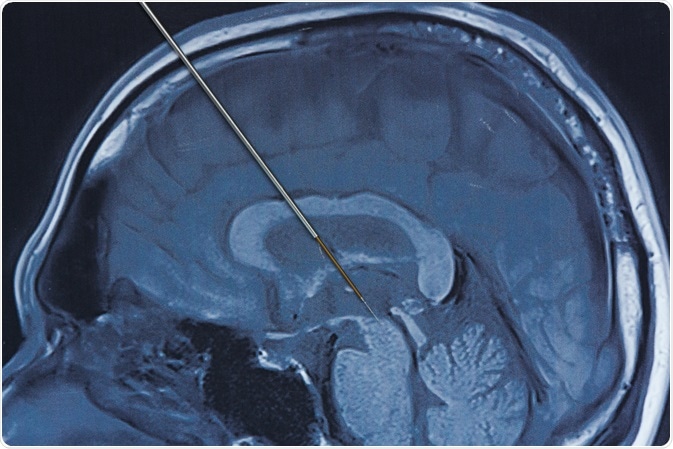

Using a microelectrode is a common method to measure oxygen consumption. A microelectrode is a biopotential electrode with an ultra-fine tapered tip. It is either inserted directly into a tissue, or an array of microelectrode needles can be placed against a tissue.

There are some drawbacks to the microelectrode method. A surface measurement can provide oxygen tension histograms over a wide field, but identification of the recording site is limited by the presence of the opaque electrode. Obtaining measurements at different sites in the field is difficult due to constant recalibration caused by the electrode having to be removed each time to take a new measurement.